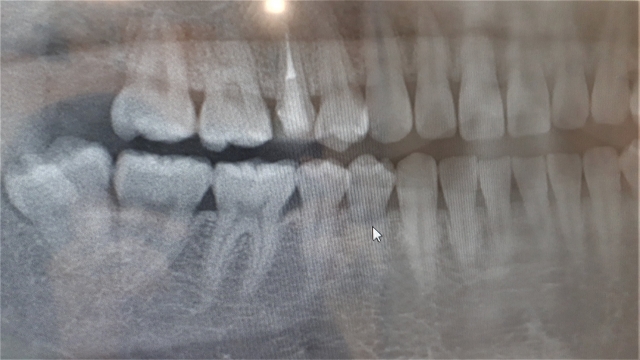

親知らずの抜歯は、難易度が高く、神経や血管の位置を正確に把握する必要があるため、歯科・口腔外科の医師に相談し、レントゲンやCT撮影などで歯の状態、根の形、周囲の神経との位置関係などを確認した上で、適切な治療法を決めていくのが最も安心で安全です。